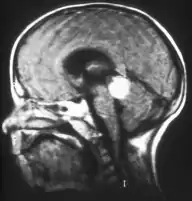

Aspect of trilateral retinoblastoma on MRI

Traditional ultrasound B scan can detect calcifications in the tumour while high-frequency ultrasound B scan is able to provide higher resolution than the traditional ultrasound and determine the proximity of the tumour with front portion of the eye. MRI scan can detect high-risk features such as optic nerve invasion; choroidal invasion, scleral invasion, and intracranial invasion. CT scan is generally avoided because radiation can stimulate the formation of more eye tumours in those with RB1 genetic mutation.[35]